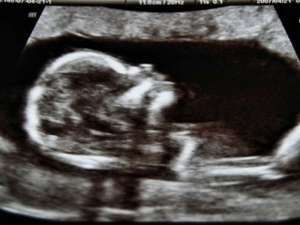

Il bambino nel secondo trimestre

Mercoledì, 21 Settembre 2016 04:53

Inizia a spuntare un pochino di pancia, la notizia può essere finalmente diffusa, i sintomi fastidiosi si affievoliscono e l'energia…